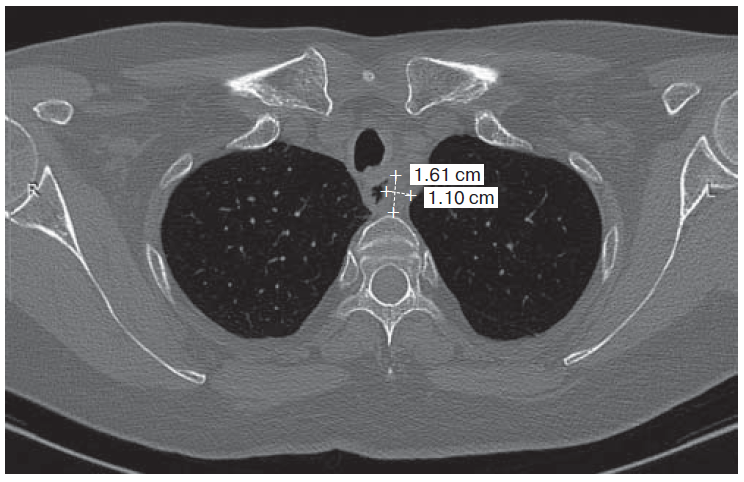

7. Fig. 6. Computer tomogram of thoracic organs cavity: soft tissue formation in the left tracheo- esophageal groove at Th1-Th2 level 16 × 13 mm. | |